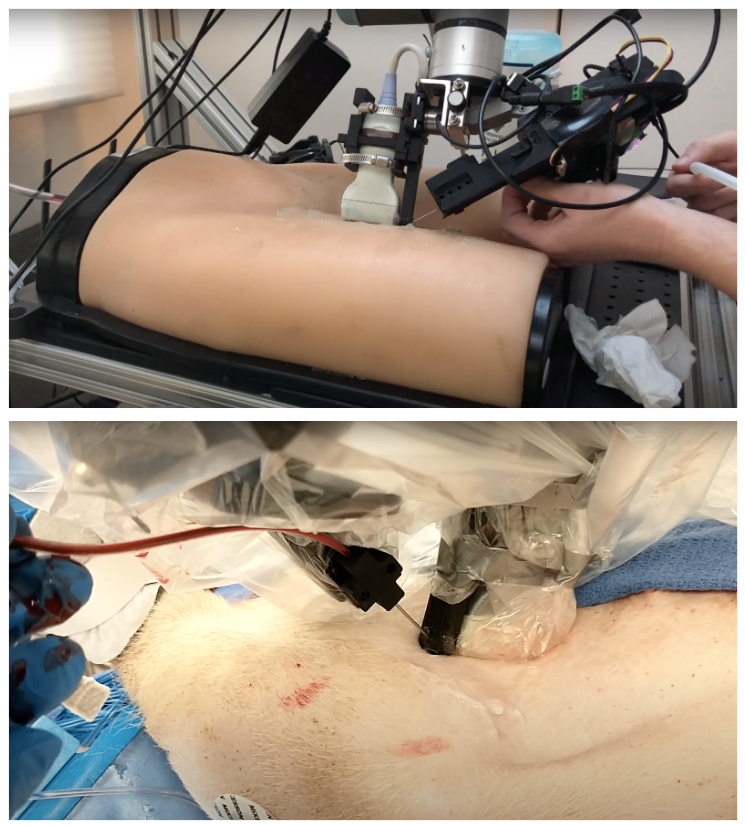

Using the system seen in Fig. 1, a single operator with no medical experience was able to gain femoral vascular access in-vivo. To the best of our knowledge this marks the first instance of a robotically assisted femoral catherization. In this paper, we will present an overview of the Seldinger technique, the medical technique we are attempting to automate, a technical breakdown of the software and hardware components required for each sub-task, and an overview of our experimental results on pigs as well as surgical phantoms. This system, though not autonomous, is the first step in the development of a fully automated system.

Our system for teleoperated needle insertion, as seen in Fig. 1, aims to mechanize the Seldinger Technique. It can be broken down into two major components highlighted in Fig. 3:

In practice femoral access is a multi handed, sometimes multi-physician task. This can pose many issues in the field of robotics where coordination between robotic systems can be very computationally expensive. To reduce the amount of manipulation and robotic degrees of freedom required we designed our hardware around single-manipulator approach. This decision has led us to the design seen in Fig.3, where both perception and insertion occur using the same manipulator.

V Results

We tested our system on a Blue Phantom Generation II Femoral lower torso training model. This allowed us to test the GUI, scanning and needle insertion in a more controlled environment than that of in-vivo studies, as well as to study the efficacy of our system on human anatomy.

V-B In-vivo results

This system presented in this paper was also used in three in-vivo porcine surgeries. In each experiment, an operator followed the procedure described in section IV. In addition, once the guidewire was placed, a catheter was slid over the guidewire and the guidewire was removed by the operator, completing the full procedure for femoral access.

These experiments differed from those performed on the phantom in several ways. First, the vasculature was much more prone to rolling, and deforming under the needle than in the phantom. In addition, the non-uniformity of the tissue could cause the needle to bend or deflect slightly. Finally, the geometry of the femoral triangle is much more curved near the femoral triangle in pigs than it is in humans.

Despite these challenges, the operator was able to use the system cannulate the femoral artery, place a guidewire, and use that guidewire to place a catheter in each of the three pigs, without causing complications such as lacerations or hematomas. While this may not be a particularly impressive feat for a trained surgeon, we consider it a great success considering the operators had no formal medical training. Though more experimentation must be undertaken to fully assess the efficacy and usability of the system, these experiments show the system’s real world operablility, and is a significant step in our goal of fully automating this procedure.